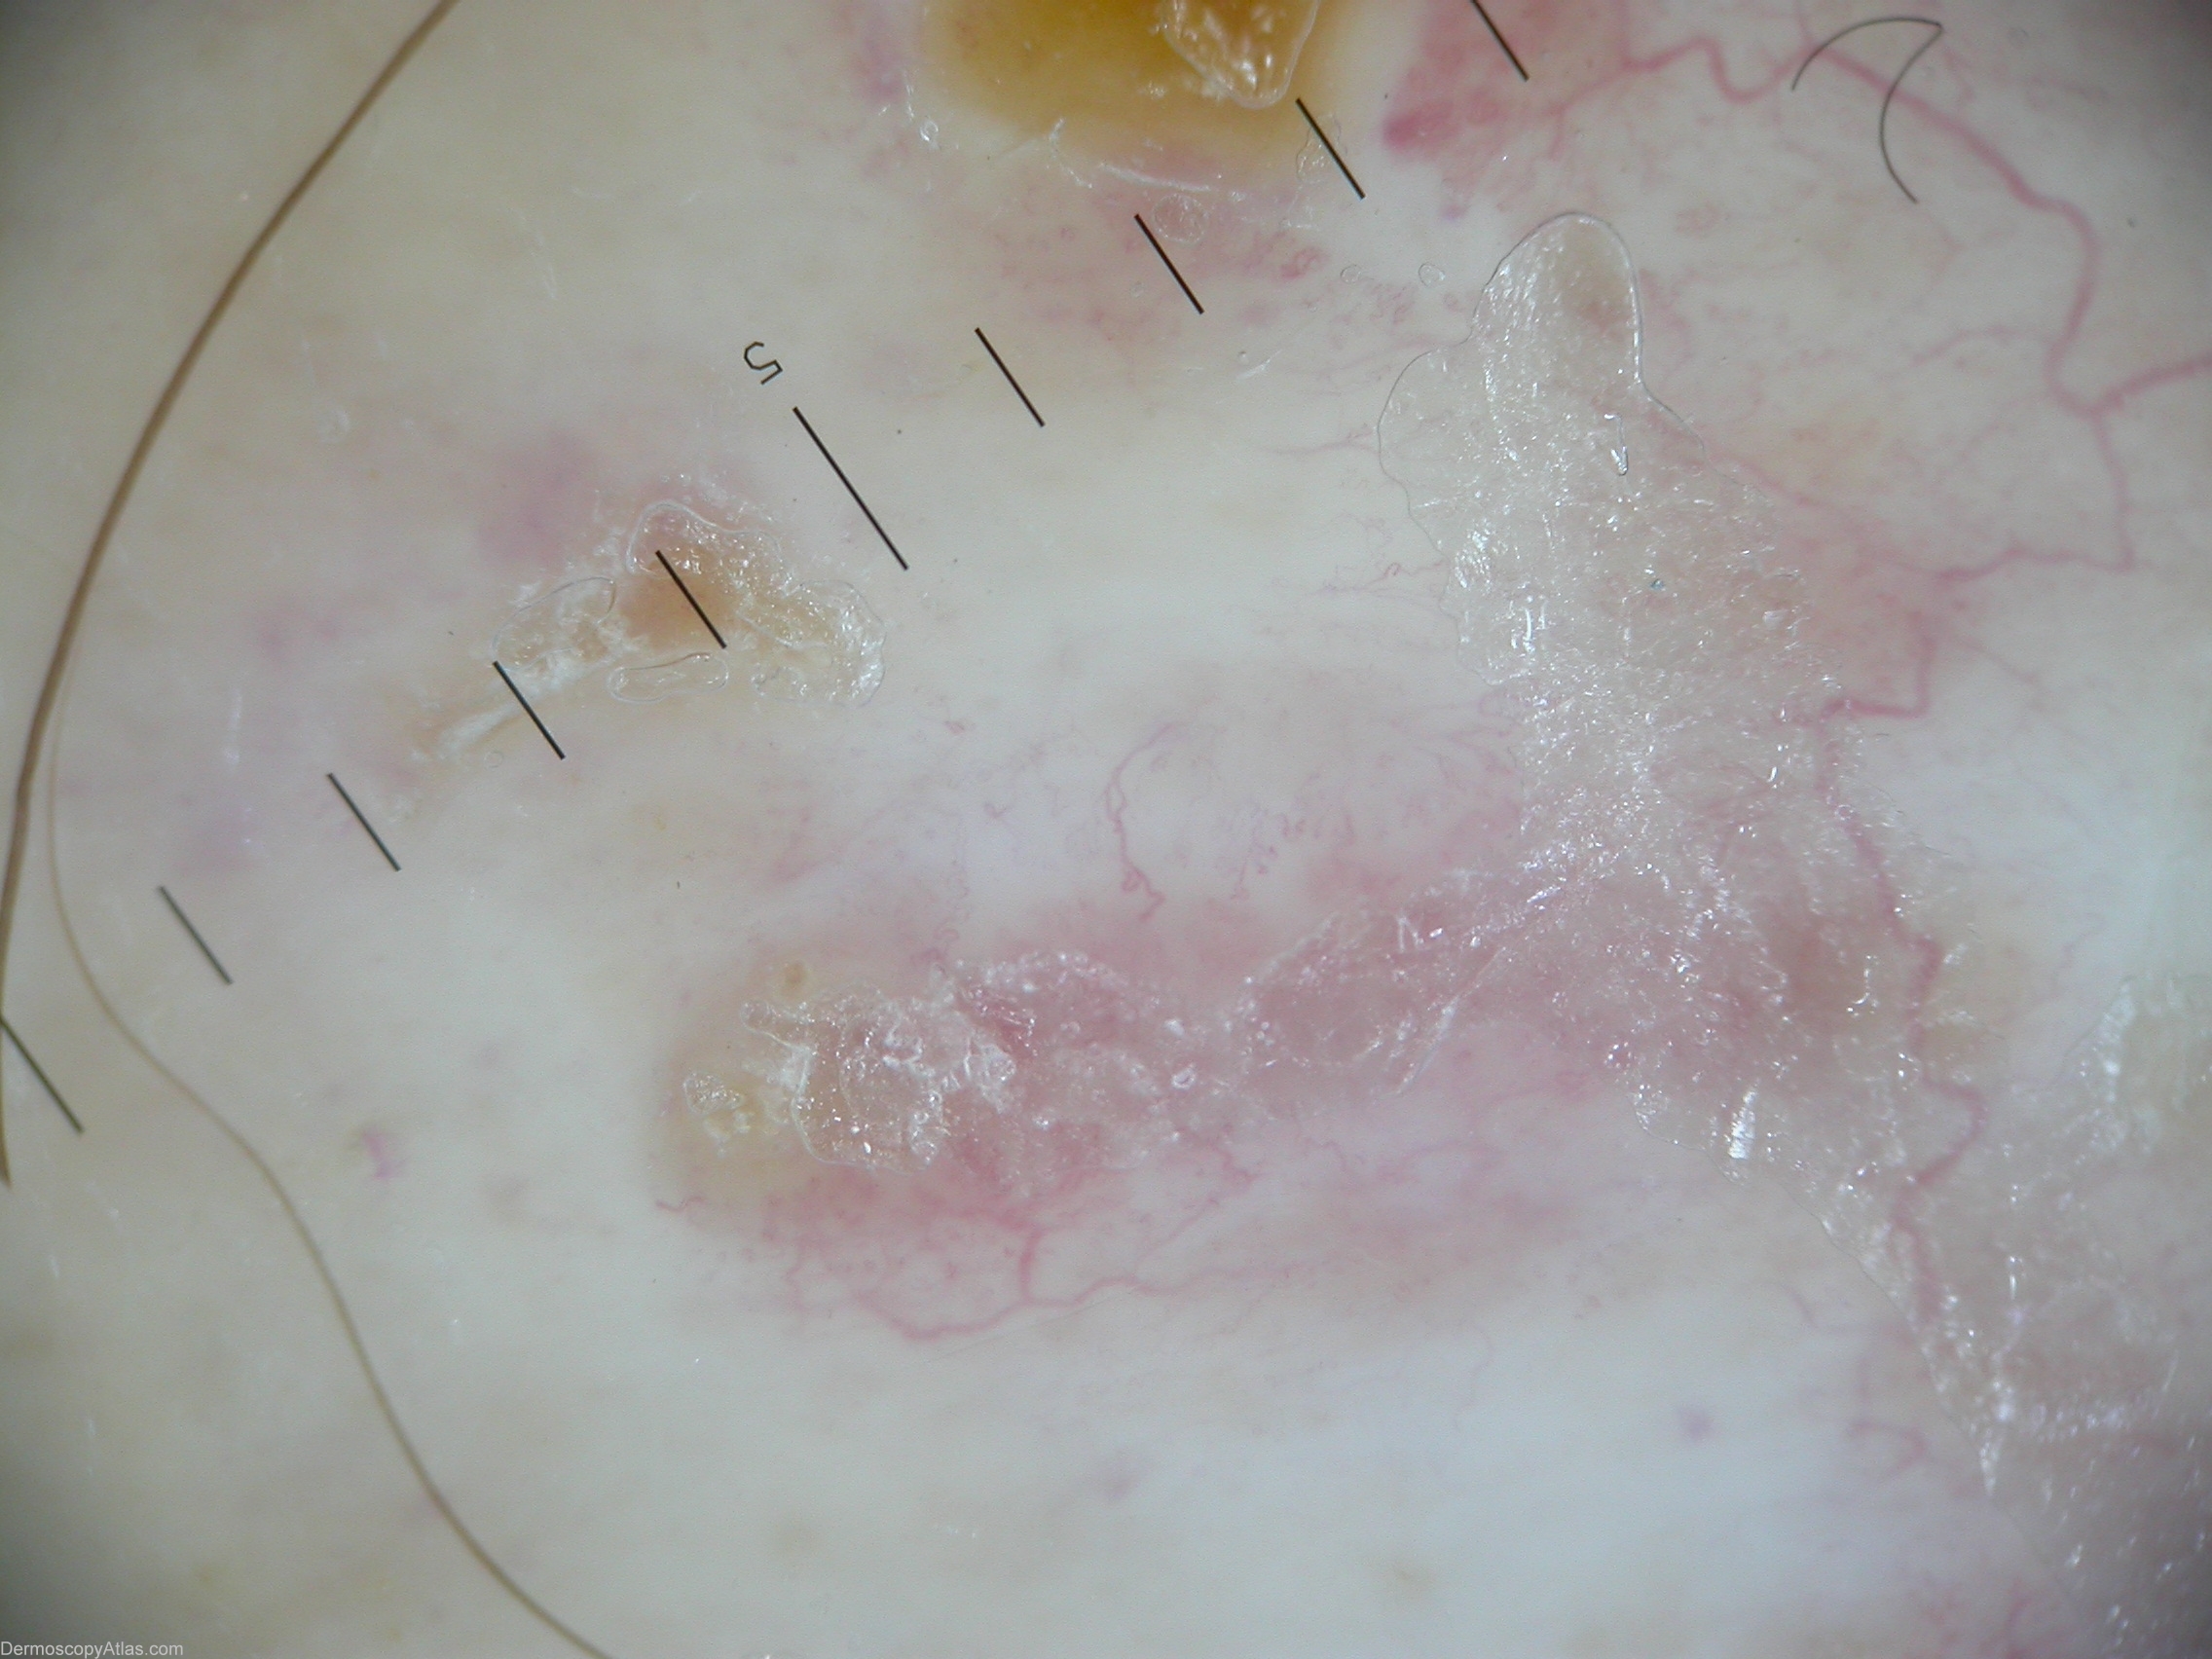

Image Number #3065 (Necrobiosis lipoidica)

Site: Leg

Diagnosis: Necrobiosis lipoidica

Description: Accentuated arborizing vessels with pearl-white areas of fibrosis.

History: This plaque continued to expand slowly one year after it appeared on the shin of a 49 year old nondiabetic woman. A biopsy showed altered collagen and granulomatous inflammation typical of necrobiosis lipoidica. Dermascopic picture of necrobiosis lipoidica could be described by accentuated arborizing vessels with pearl-white areas of fibrosis.